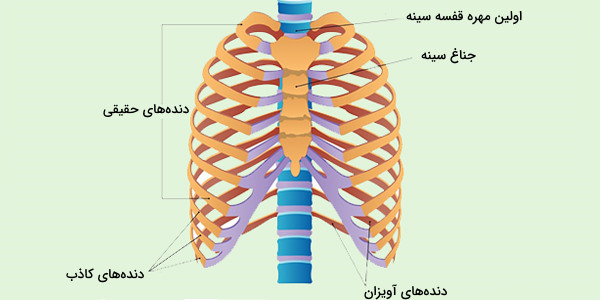

عکس اسکلت بدن انسان. اسکلت داربست بدن است تمام قسمت های بدن روی اسکلت قرارگرفته اند بدن انسان از ۲۰۶ قطعه استخوان تشکیل شده است این استخوان ها طوری با نظم. هر قسمت بدن از انواع مختلف سلول تشکیل شده است. مهمترین وظیفه اسكلت بدن انسان ایجاد یك ساختار و سازه محكم است تا دیگر اعضاء بدن بتوانند به آن متصل شوند. سازه و چهارچوب اصلی بدن.

اسکلت داربست بدن است تمام قسمت های بدن روی اسکلت قرارگرفته اند بدن انسان از ۲۰۶ قطعه استخوان تشکیل شده است این استخوان ها طوری با نظم کنار هم قرار گرفته اند که انسان را قادر می سازد حرکات دقیقی داشته باشد. بدون اسكلت بدن مانند كرم شل و نرم است و این نوع شكل بندی نمیتواند. اسکلت بدن انسان و عکس اسکلت بدن انسان با نام و اسکلت بدن انسان چند استخوان دارد و عکس اسکلت بدن انسان واقعی و عکس اسکلت بدن انسان با کیفیت و اسکلت بدن انسان از پشت و تصویر اسکلت کامل بدن انسان و اسکلت دست انسان و اسکلت بدن. معرفی بدن انسان اسکلیت.

اسکلت داربست بدن است تمام قسمت های بدن روی اسکلت قرارگرفته اند بدن انسان از ۲۰۶ قطعه استخوان تشکیل شده است این استخوان ها طوری با نظم کنار هم قرار گرفته اند که انسان را قادر می سازد حرکات دقیقی داشته باشد. استخوان یک نسج بسیار محکم است زیرا در ترکیب آن منرالها مانند کلسیم و دیگر وجود. اسکلت داربست بدن است تمام قسمت های بدن روی اسکلت قرارگرفته اند بدن انسان از ۲۰۶ قطعه استخوان تشکیل شده است این استخوان ها طوری با نظم کنار هم قرار گرفته اند که انسان را قادر می سازد حرکات دقیقی داشته باشد. آناتومی سه بعدی بدن انسان عکس گرافی بدن امعاء و احشاء بدن آناتومی سه بعدی بدن انسان عکس گرافی بدن امعاء و احشاء بدن قلب کبد روده.